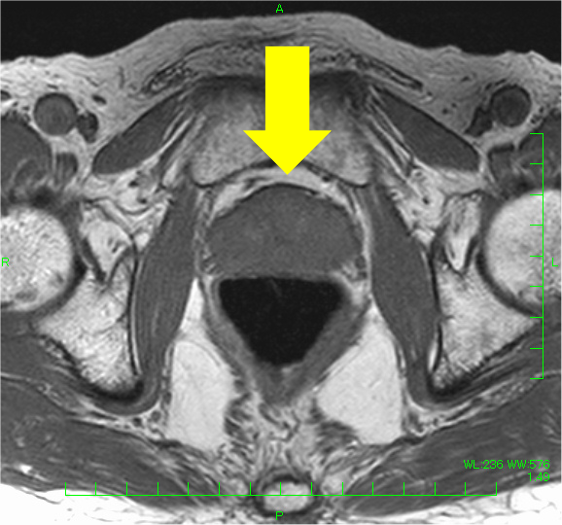

検診でPSA 4.9と上昇があり、MRIが施行された。左移行域に14mmの病変を認め、T2強調像で低信号(PI-RADS v2.1スコア4)、拡散強調像で高信号・Appar-ent Diffusion Coefficient(ADC)低下(スコア4)、ダイナミックで早期濃染を示し、PI-RADS v2.1でカテゴリー4と判定され前立腺癌が疑われた。一方、辺縁域はT2強調像で不均一低信号を呈したが、結節様の拡散強調像での強い高信号、ADC低下はなく、ダイナミックMRIでも結節様の早期濃染はなく、びまん性遷延性の染まりがみられたことから炎症性変化と判断した。生検が行われ、癌の診断であった。その後、ロボット支援下根治的前立腺摘除術が施行され、MRIと一致した前立腺癌の診断を得た(Gleason score 4+3=7, pT2N0)。

本症例では、左移行域腹側の病変(14mm、T2強調像:低信号(スコア4)、拡散強調像:高信号・ADC:低下(スコア4)、ダイナミック:早期濃染: PI-RADS v2.1カテゴリー4)は、前立腺癌の判定が容易であった。一方、辺縁域はT2強調像でびまん性に不均一な低信号を呈し、癌の評価が難しい方であった。左辺縁域に小結節様のT2強調像にて低信号がみられ、拡散強調像やADCの所見は明瞭でなく癌の可能性は低いと考えたが、T2強調像での信号が明瞭で、癌を否定してよいのか悩ましい。本症例では、ダイナミックMRIも施行しており、左移行域腹側病変は早期濃染―washout パターンを呈したが、左辺縁域の小結節に早期濃染はなく、両側辺縁域とも遷延性の染まりを認めたため、辺縁域に癌はなく、両側辺縁域に炎症性変化があると断定できた。病理的にも、MRIで指摘した病変部のみ癌が同定され、その他の領域に癌はなかった。